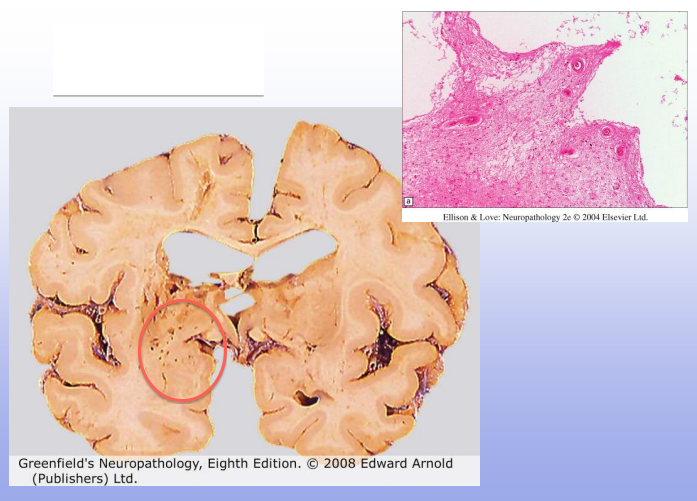

CADASIL: cerebral autosomal dominant arteriopathy with subcortical ischemia and leukoencephalopathy

see small lacunar infarcts (red circle)

Hypertensive hemorrhage; tend to occur more centrally in brain (basal ganglia, thalamus)

Top R: Charcot-Bouchard aneurysm of lenticulostriate vessels of BG, associated wit HTN

Bottom R: thickened BV wall, loss of SM